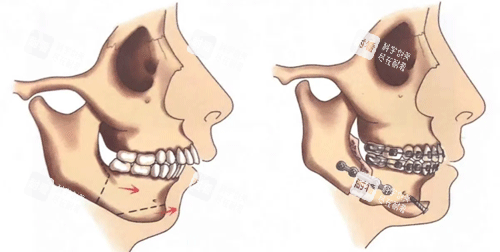

颏成型手术36800起,主要是针对下巴进行调整。下巴对一个人的面部美观影响可大啦!有些人下巴比较短,会显得面部比例不协调;还有些人下巴后缩,侧面看起来就不太好看。通过颏成型手术,就能让下巴变得更加较好。手术后,下巴的形态会更加自然,面部比例也会更加协调,从侧面看过去,整个面部线条都变得更加立体了。

很多在罗恩医生这里做过手术的患者都给出了非常好的反馈。有做下颌角和颧骨内推手术的患者说,术后朋友都说自己瘦了,完全看不出动过骨头,结果非常自然,就像是天生的一样。还有做地包天矫正手术的患者说,终于能啃排骨了,术后咬合比术前还舒服。这些真实的反馈都说明了罗恩医生的手术技术确实很不错,不仅能改善面部外观,还能提升口腔的功能。而且啊,罗恩医生做过的手术有零失败记录,这就大大降低了“翻车风险”。对于患者来说,手术结果有维持,心里就更放心啦!